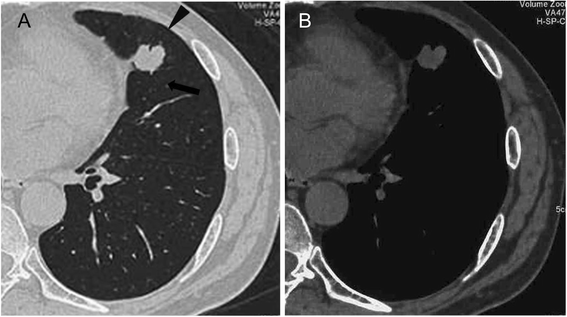

Cavitary Lung Metastasis As Relapse Of Prostate Cancer Sciencedirect. Prostate cancer metastasis occurs when cells break away from the tumor in the prostate. The bones, brain, liver, and lungs are common sites of cancer metastasis. Webmd explains what metastatic prostate cancer is and how it is found. The prostate is a gland in the male reproductive system that surrounds the urethra just below the bladder. Prostate cancer metastasis occurs when cells break away from the tumor in the prostate. If your prostate cancer spreads to other parts of your body, your doctor may tell you that it's metastatic or that your cancer has metastasized. Most prostate cancers are slow growing. Learn about metastatic lung cancer symptoms, causes, and when cancer cells travel to other organs in the body, it's called metastasis. A pulmonary metastasis of prostate cancer in the absence of osseous or lymph node metastases is an extremely rare finding. Prostate cancer metastasis — find out where prostate cancer spreads. Prostate cancer is cancer of the prostate. Rare locations of prostate cancer metastasis include When prostate cancer metastasizes to the following areas, it can cause a range of complications. Distant metastasis means that prostate cancer has spread beyond the pelvis. Metastatic lung cancer occurs when cancer in another area of the body spreads to the lung.

A Prostate Cancer Patient With Isolated Lung Metastases A Case Report Wu Translational Cancer Research. If your prostate cancer spreads to other parts of your body, your doctor may tell you that it's metastatic or that your cancer has metastasized. Prostate cancer is cancer of the prostate. Prostate cancer metastasis — find out where prostate cancer spreads. Prostate cancer metastasis occurs when cells break away from the tumor in the prostate. Rare locations of prostate cancer metastasis include When prostate cancer metastasizes to the following areas, it can cause a range of complications. The bones, brain, liver, and lungs are common sites of cancer metastasis. The prostate is a gland in the male reproductive system that surrounds the urethra just below the bladder. A pulmonary metastasis of prostate cancer in the absence of osseous or lymph node metastases is an extremely rare finding. Most prostate cancers are slow growing. Distant metastasis means that prostate cancer has spread beyond the pelvis. Learn about metastatic lung cancer symptoms, causes, and when cancer cells travel to other organs in the body, it's called metastasis. Metastatic lung cancer occurs when cancer in another area of the body spreads to the lung. Webmd explains what metastatic prostate cancer is and how it is found. Prostate cancer metastasis occurs when cells break away from the tumor in the prostate.